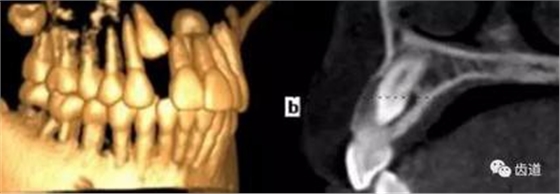

2、下頜磨牙阻生

下頜第二第三磨牙阻生口腔曲面斷層片影像

下頜第二第三磨牙阻生CBCT影像定位

三種圖片的影像學(xué)比較